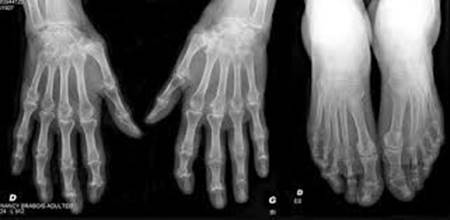

DPC PERTINENCE DES PRESCRIPTIONS D'ACTES DE RADIOLOGIE INTERVENTIONNELLE OSTÉO-ARTICULAIRE

AMELIORER LA PERTINENCE DES PRESCRIPTIONS RADIOLOGIQUES INTERVENTIONNELLES OSTEOARTICULAIRES